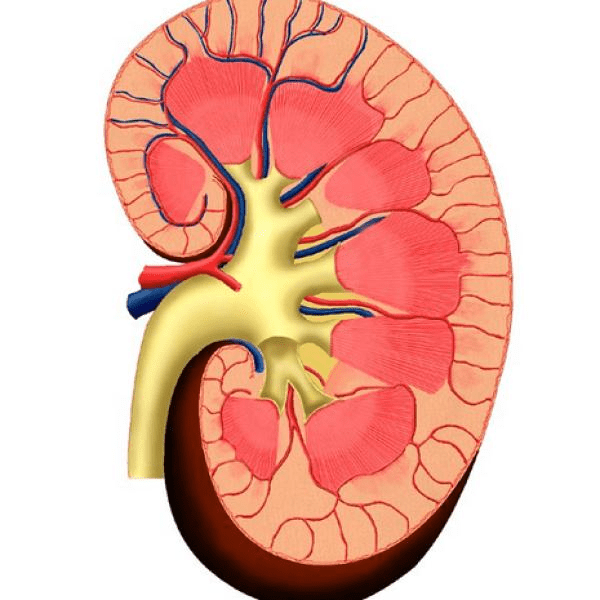

Son los médicos especialistas en ayudarle cuando tenga problemas de insuficiencia renal.

Médico Nefrólogo